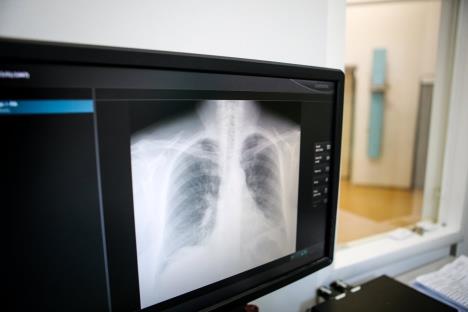

Iako se simptomi raka pluća najčešće pojavljuju tek kada je bolest u uznapredovaloj fazi, neki od njih mogu biti alarm da se javite lekaru - kašalj, infekcije, iskašljavanje krvi, nedostatak daha, bol u plućima, konstantan umor, gubitak apetita i naglo mršavljenje.